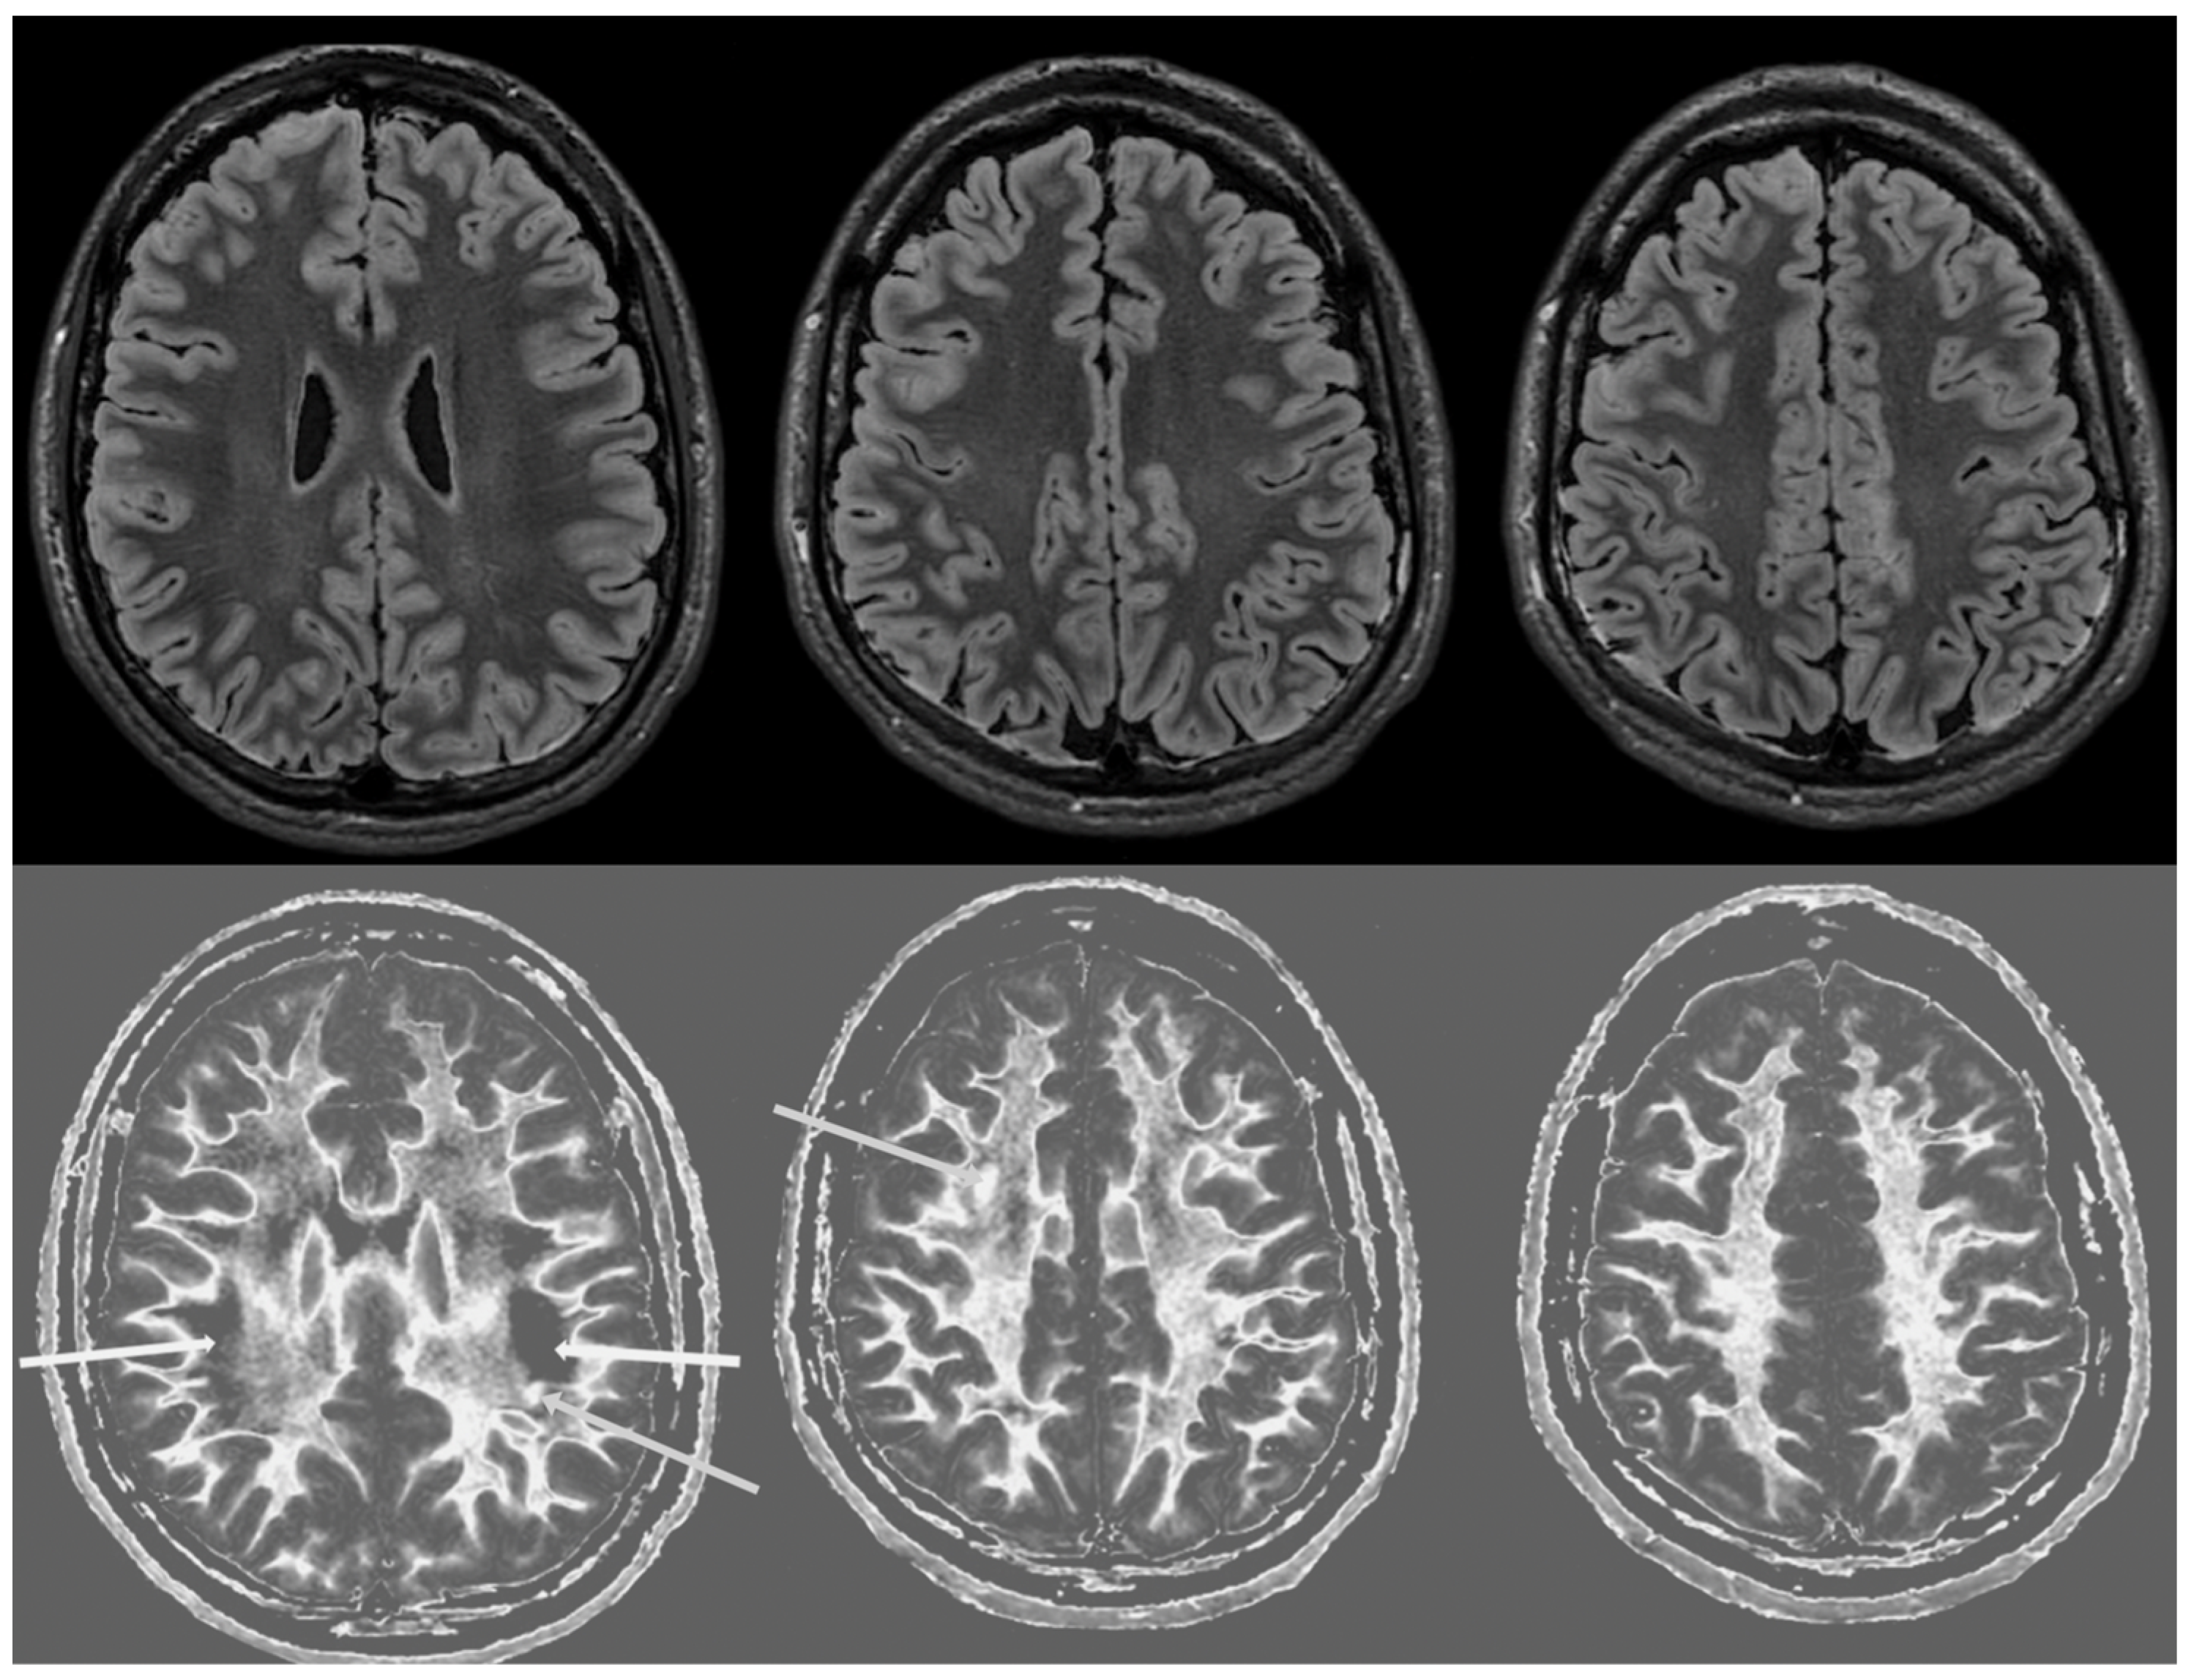

Figure 6 and Figure 7 show T2-FLAIR images (upper rows) with positionally matched dSIR images (lower rows). No abnormalities are seen in the white matter on the T2-FLAIR images, but very extensive high signal abnormalities are seen in the white matter of the corresponding dSIR images. There is relative sparing of the anterior central corpus callosum and, to a lesser extent, the posterior central corpus callosum. There is also some sparing of the peripheral white matter in the cerebral hemispheres.

Overall, the MRI findings in Case 2 are very similar to those in Case 1, as shown in Figure 4 and Figure 5. They have been described as a whiteout sign. This often involves 80% or more of the white matter in the cerebral and cerebellar hemispheres having an abnormal high signal appearance.

Figure 7. Case 2 was examined two years after his asphyxial episode. Comparison of positionally matched T2-FLAIR images (upper row) and narrow mD dSIR images (lower row). No abnormality is seen on the T2-FLAIR images, but there are extensive areas of high signals in the central white matter of the brain (lower row). Only some of the peripheral white matter on the lower images appears darker and looks more normal on the dSIR images.